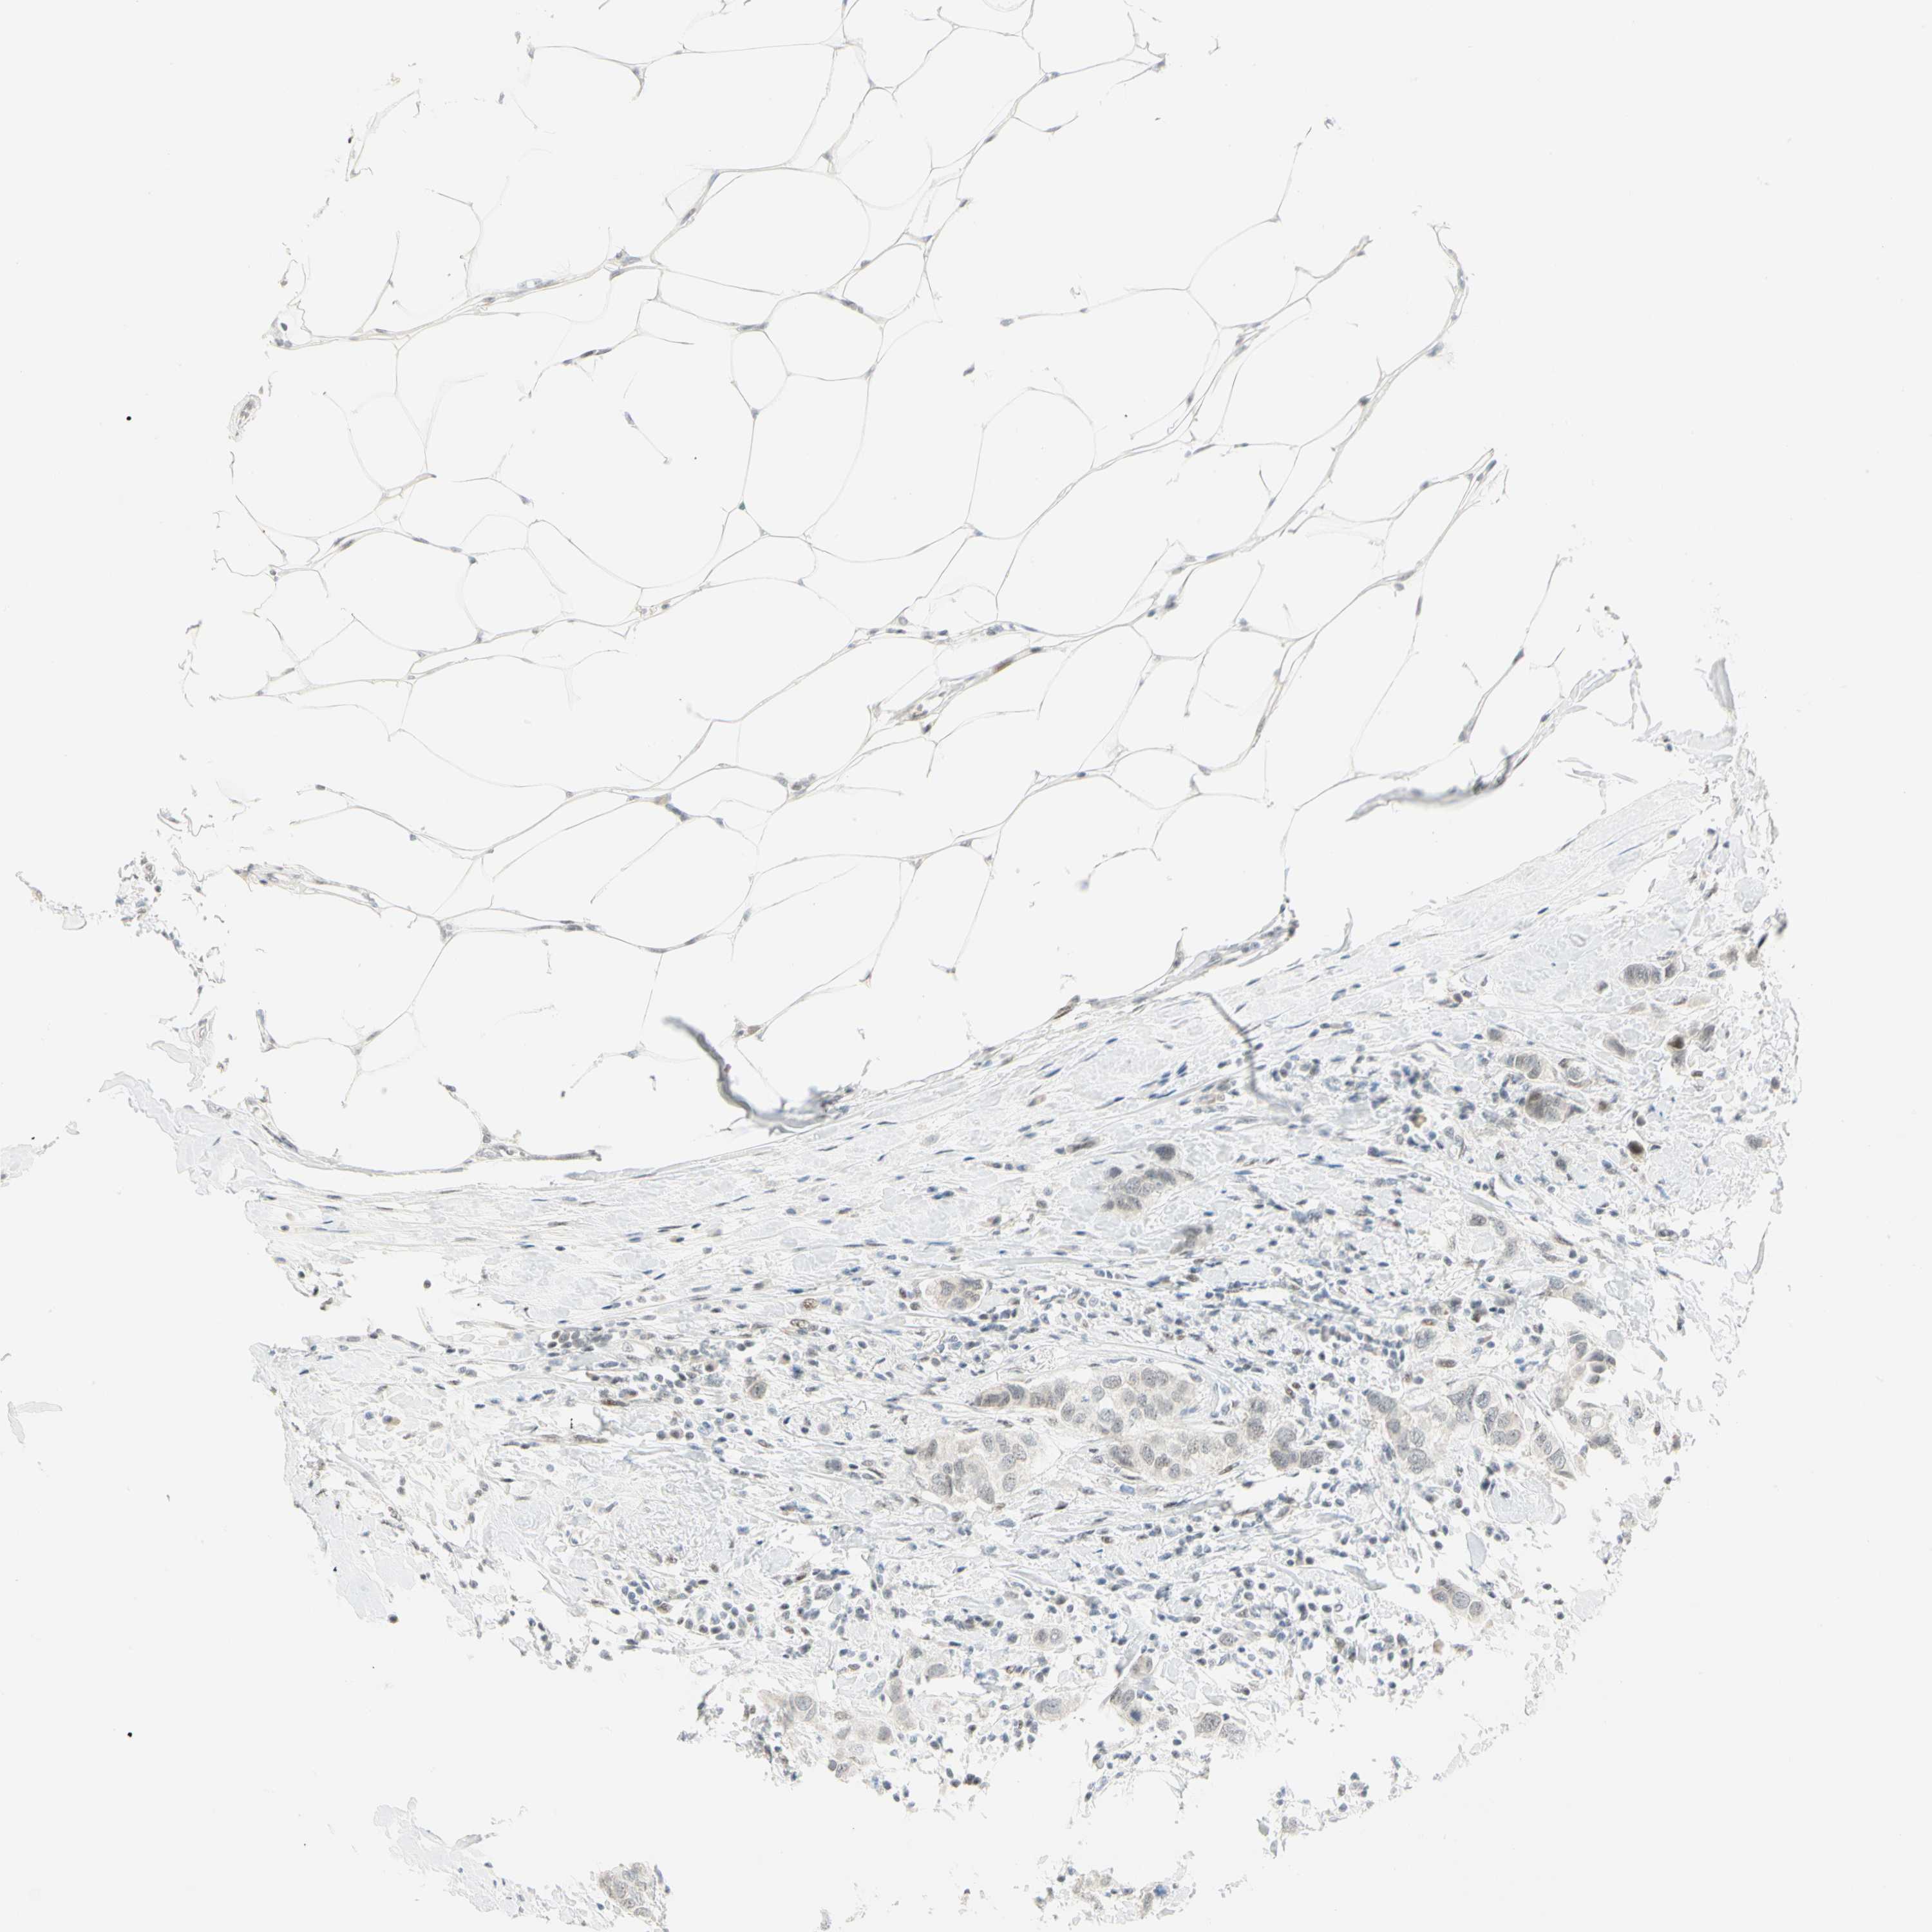

CANCER BREAST CANCER Show tissue menu

BRCA TCGA BRCA VALIDATION PROTEIN EXPRESSION